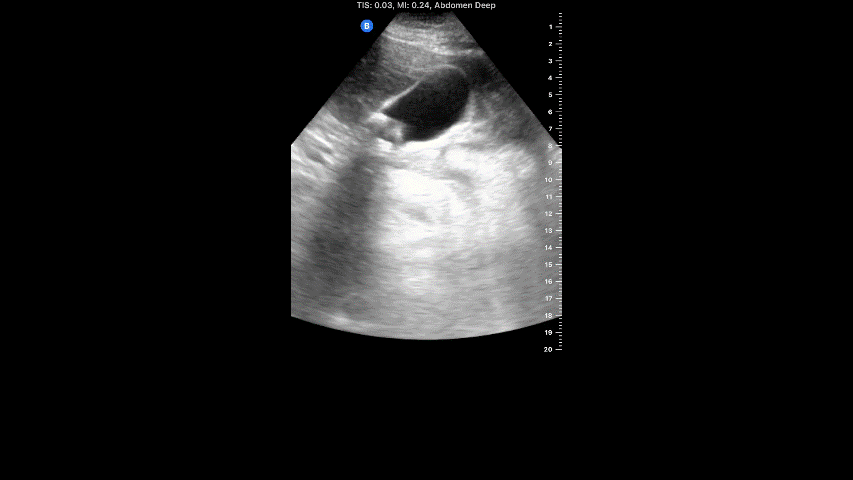

This characteristic ultrasound artifact is associated with the gallbladder stone shown in this clip. (note: name the ultrasound artifact)

What is posterior acoustic shadowing associated with gallstone?